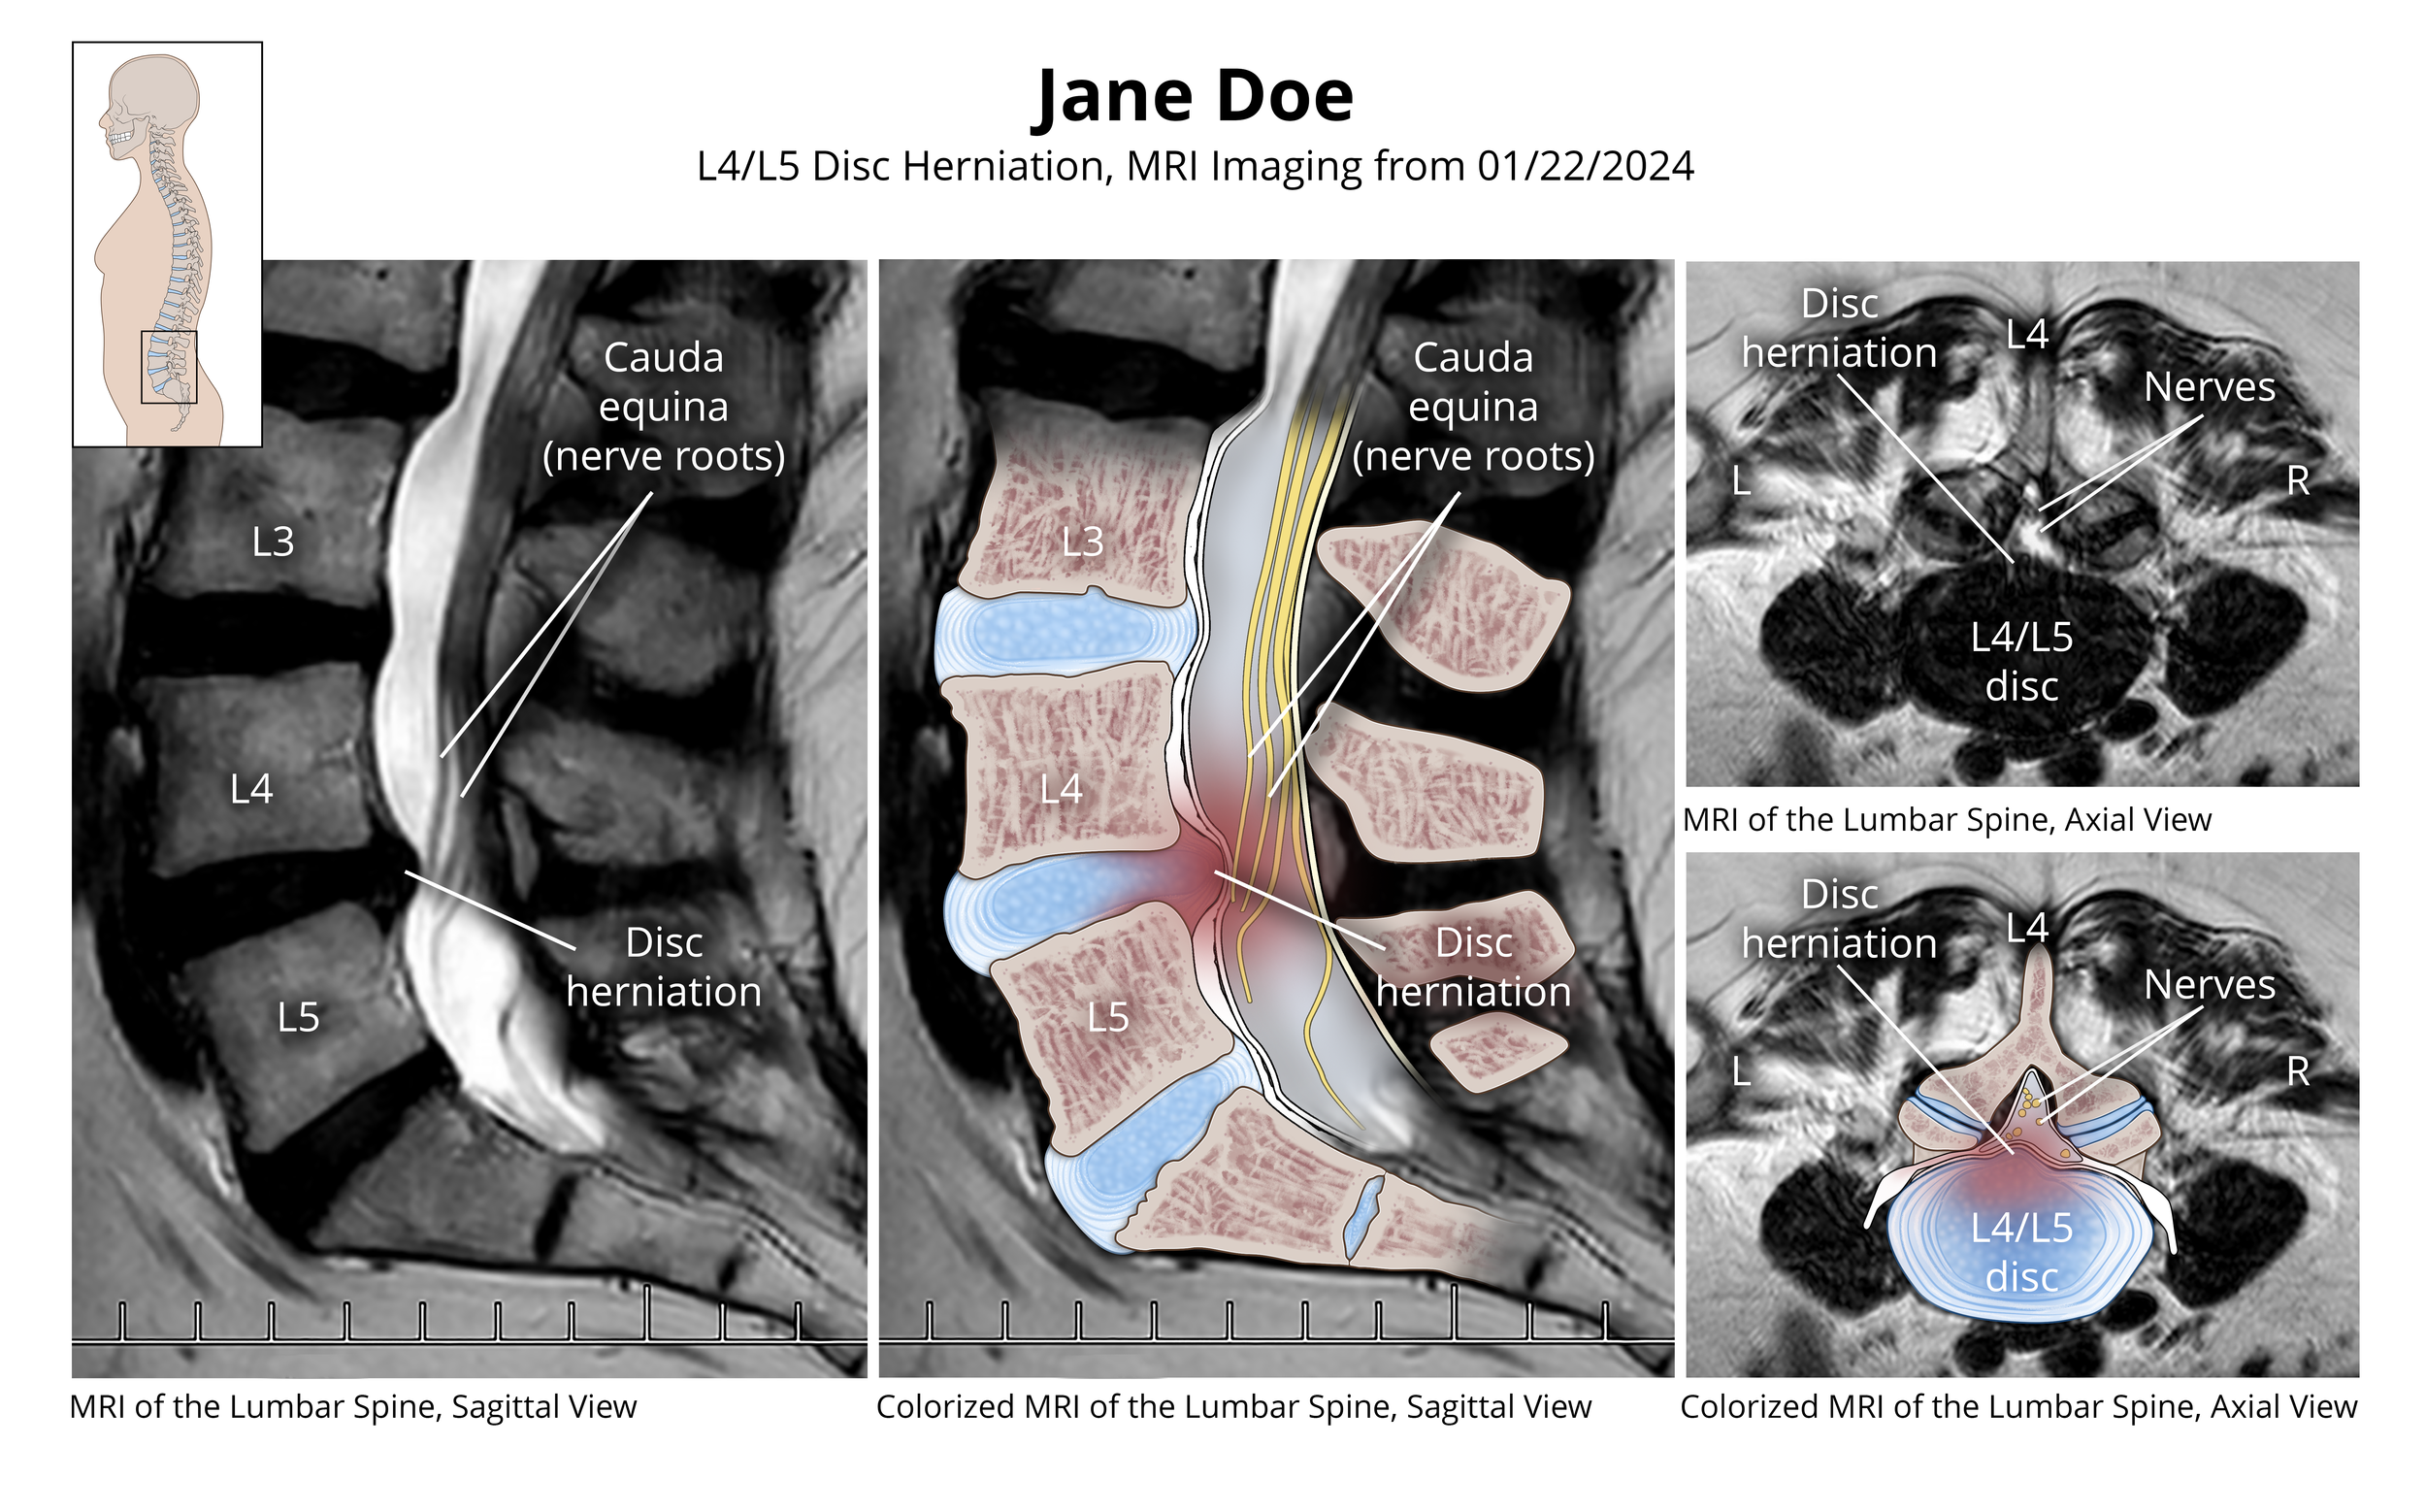

L4/L5 Disc Herniation

Overlaid Lumbar MRI demonstrating an L4/L5 herniation.